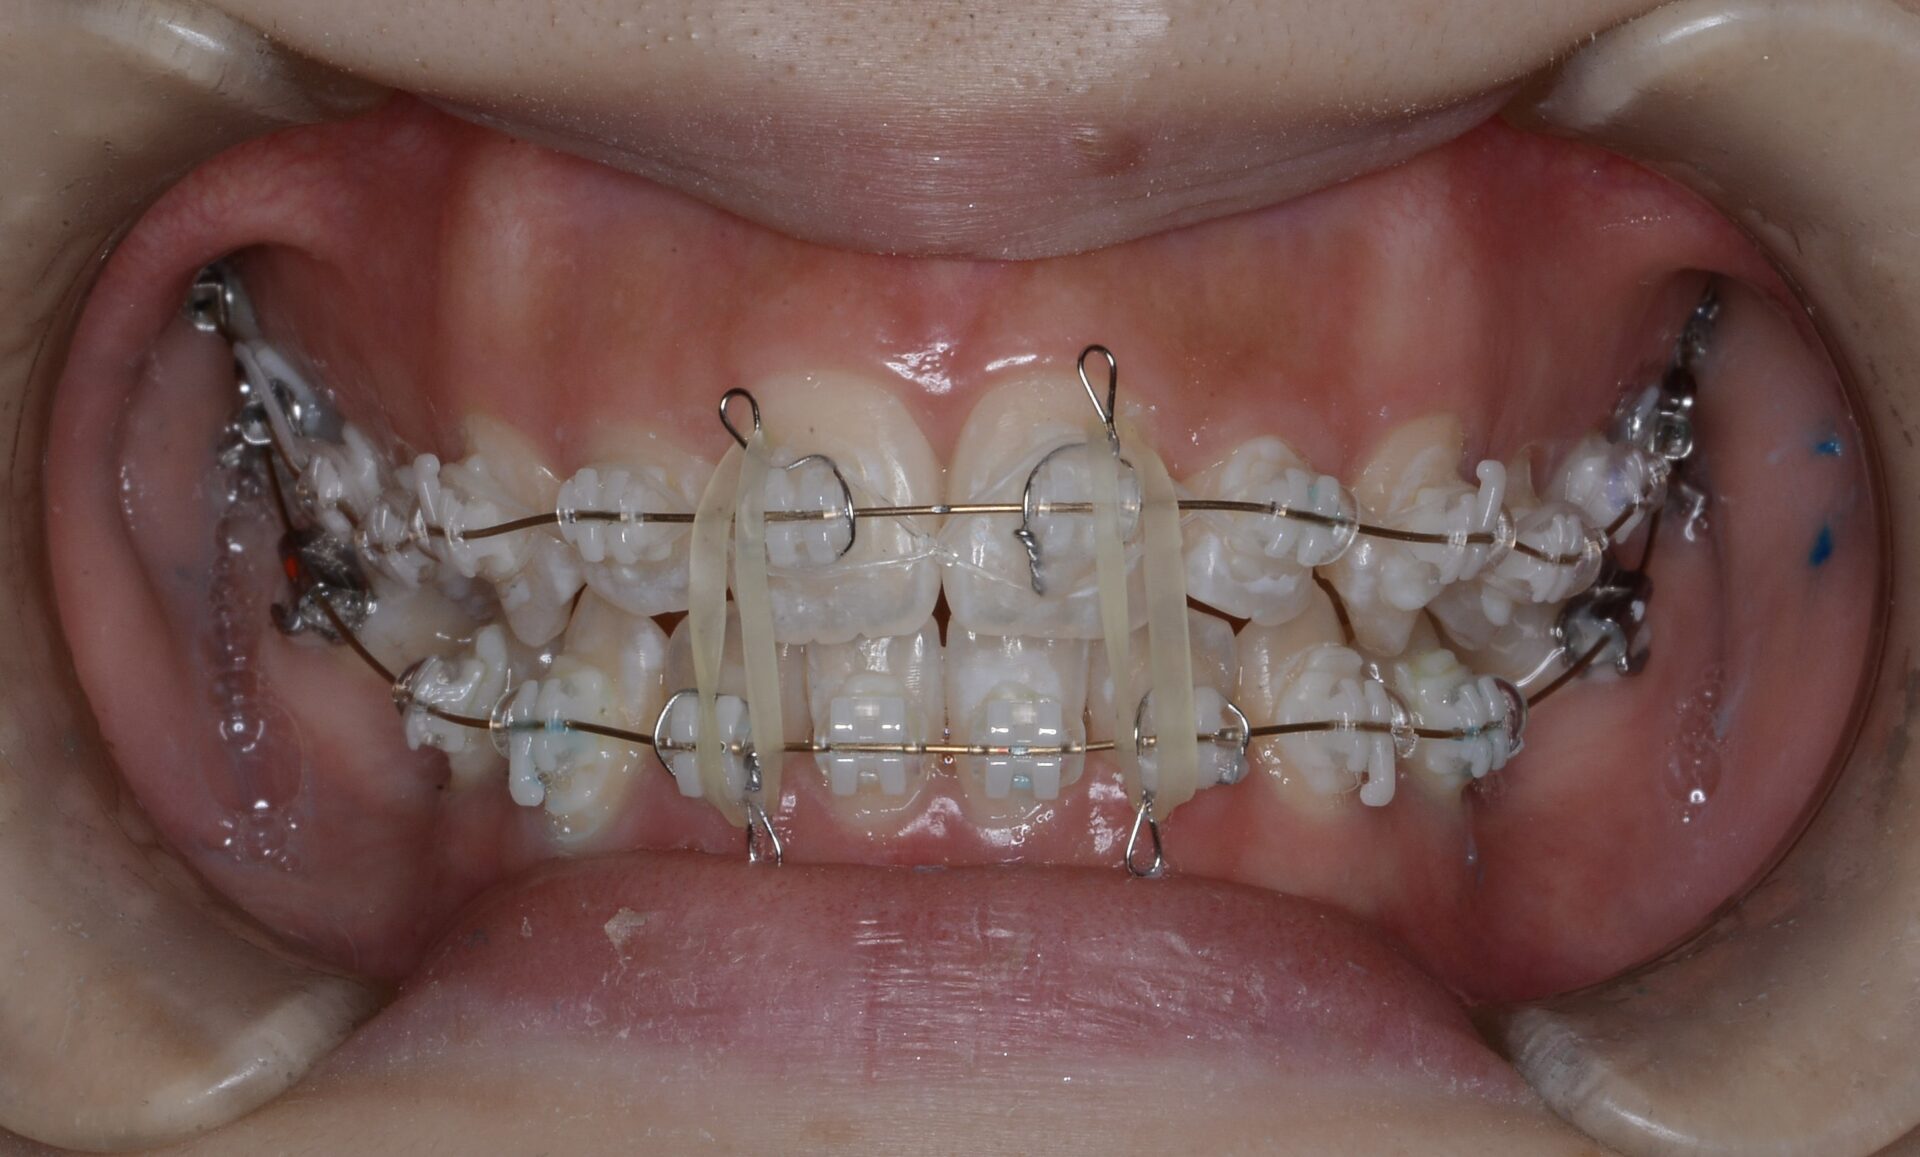

矯正治療スタート時(正面)

臼歯部の傾斜がかなり急である。

矯正治療中

智歯を抜歯してそのスペースを利用して大臼歯を遠方へ起こしつつ圧下していく。